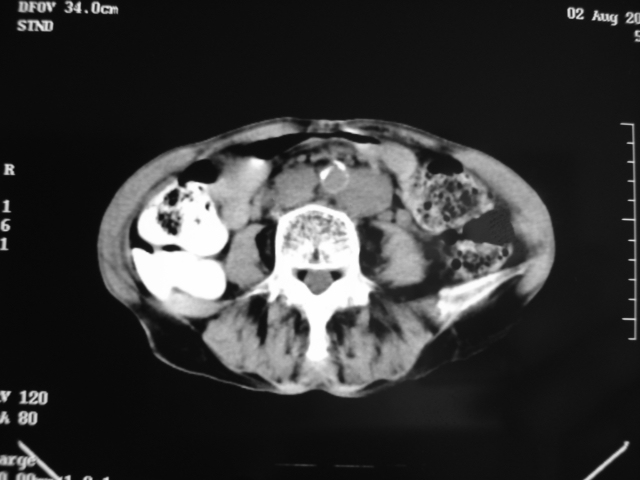

同事奶奶,73岁,腹痛一年,夜晚较重,潜血+++,拒绝增强,考虑左肾ca并腹膜后转移;请各位老师帮忙看看,谢谢!

左肾癌侵及输尿管上段,腹膜后多发淋巴结转移,脾脏钙化灶。至于潜血+++,要考虑消化道病变,本次ct片肠腔未见明显异常。

1)考虑左肾癌侵犯肾盂并腹膜后淋巴结转移。2)脾脏钙化灶。

考虑左肾癌侵犯肾盂并腹膜后淋巴结转移。